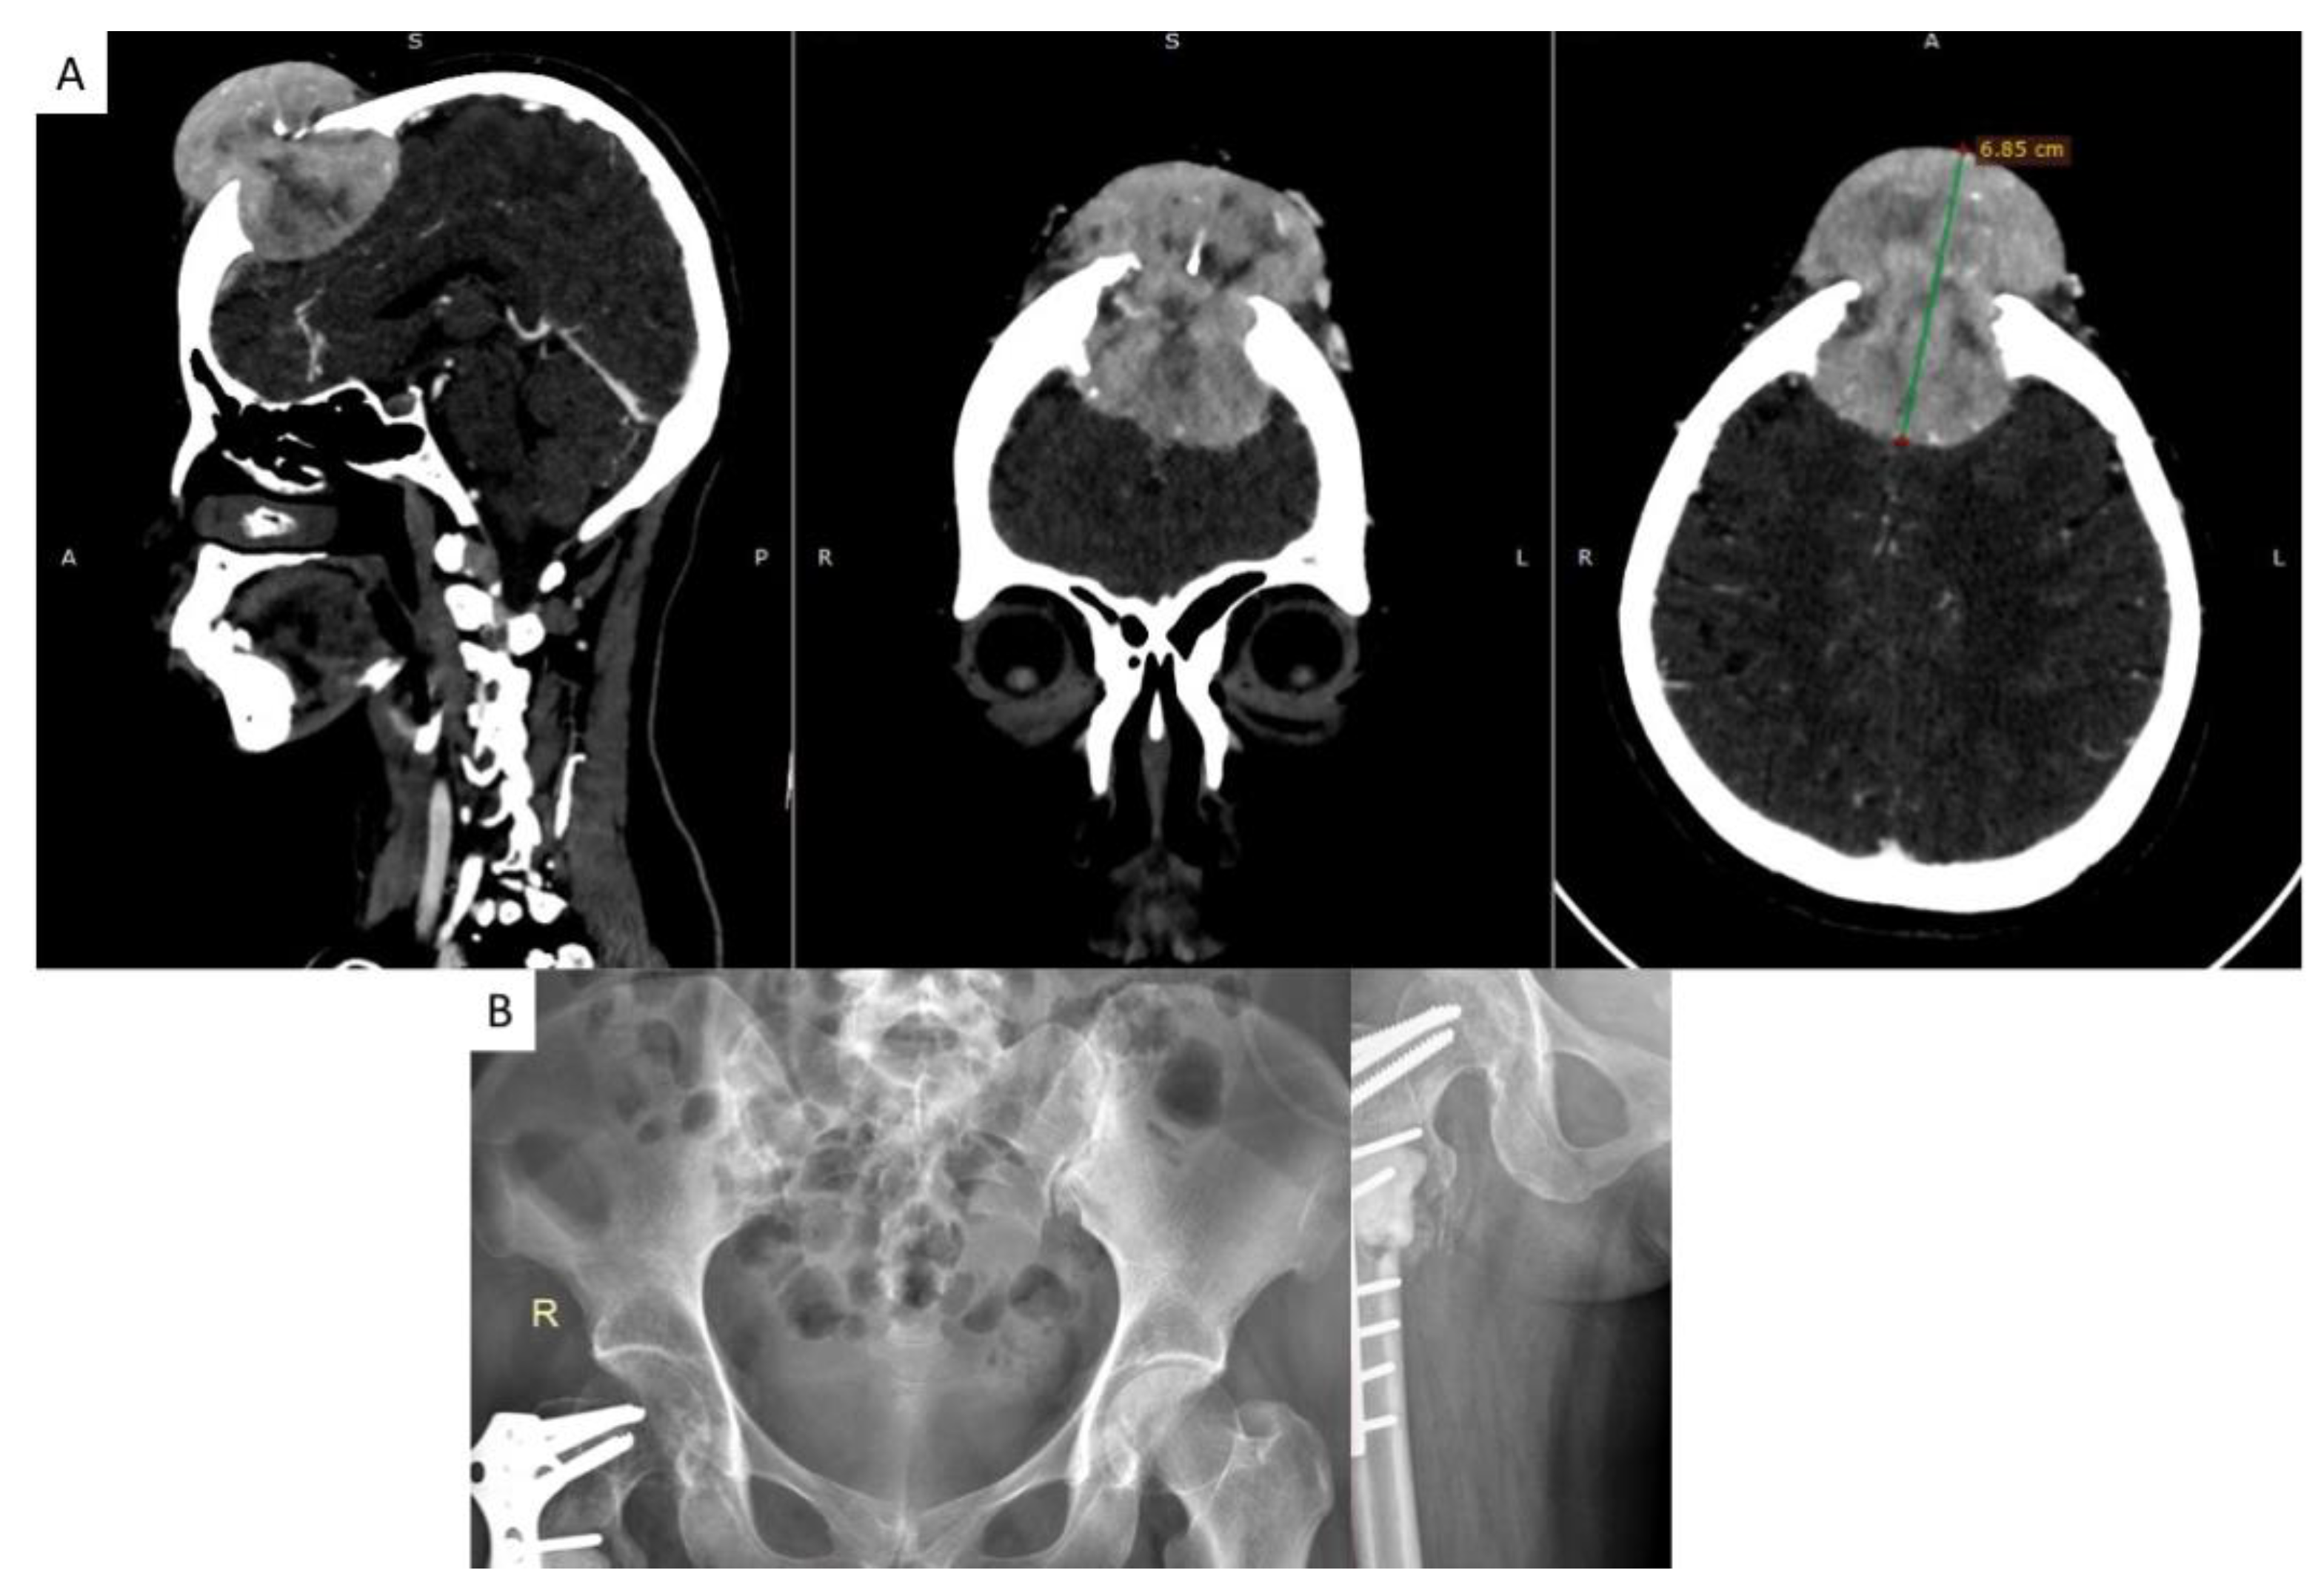

2.2. Diagnosis